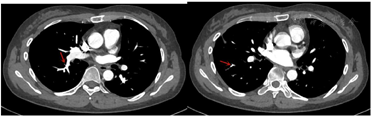

4个月后门诊复查CTPA结果提示血栓病灶较前明显缩小,无新发血栓征象(图2)。考虑患者存在多种免疫介导疾病,建议终身口服华法林抗凝,监测INR(2-3),定期呼吸科与风湿科随访。